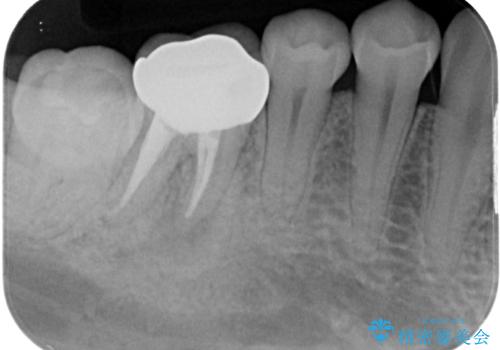

その後、ファイバーコア(グラスファイバー製の支台)を築造し、最終的には精密な適合性と審美性に優れたオールセラミッククラウンによる補綴をしました。

根管治療後の歯は、再感染を防ぐために精密なクラウンで補綴することが非常に重要です。